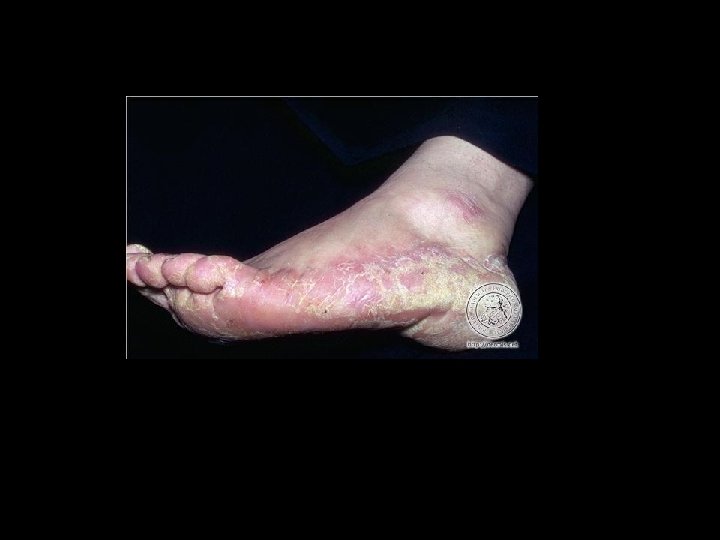

Tiña de los Pies • Es una de las localizaciones mas frecuentes en los hombre adultos. • Denominado también pie de atleta. • Las condiciones que la predisponen: calor, humedad, maceración, tratamientos inducidos, terreno inmunodeprimido.

Tiña de los Pies • Especies causales : T. mentagrophytes E. floccosum. • Se adquieren en piscinas, gimnasios, clubs, baños, trabajadores y deportistas.

Cuadro clínico • Cuando predomina entre los dedos, sobre todo en el primer espacio del dedo pequeño y el segundo se habla de la forma intertriginosa. • Se observan zonas maceradas con mucha escama.

Forma vesiculosa • Se caracteriza por la presencia de pequenas vescículas que se rompen dejando erosiones y costras melicéricas y también mucho prurito. • Las vescículas pueden verse entre los dedos y bordes de los pies.

Forma hiperqueratósica • Escamas extensas, a veces muy gruesa, callosa. • Por lo general se combinan todos los tipos en este tipo de lesiones.

Complicaciones • Dermatitis de contacto : por la aplicación de varios medicamentos. • Se observan los pies con edema , más vesículas o ampollas, costras melicericas

Complicaciones • Impetiginización : complicación a causa del rascado • Se presentan pústulas y costras melicéricas acompañadas de dolor • Los pies se edematizan, en ocasiones adenopatía inguinal y febrícula. • Brotes de vesículas en las manos, entre los dedos y en las palmas.